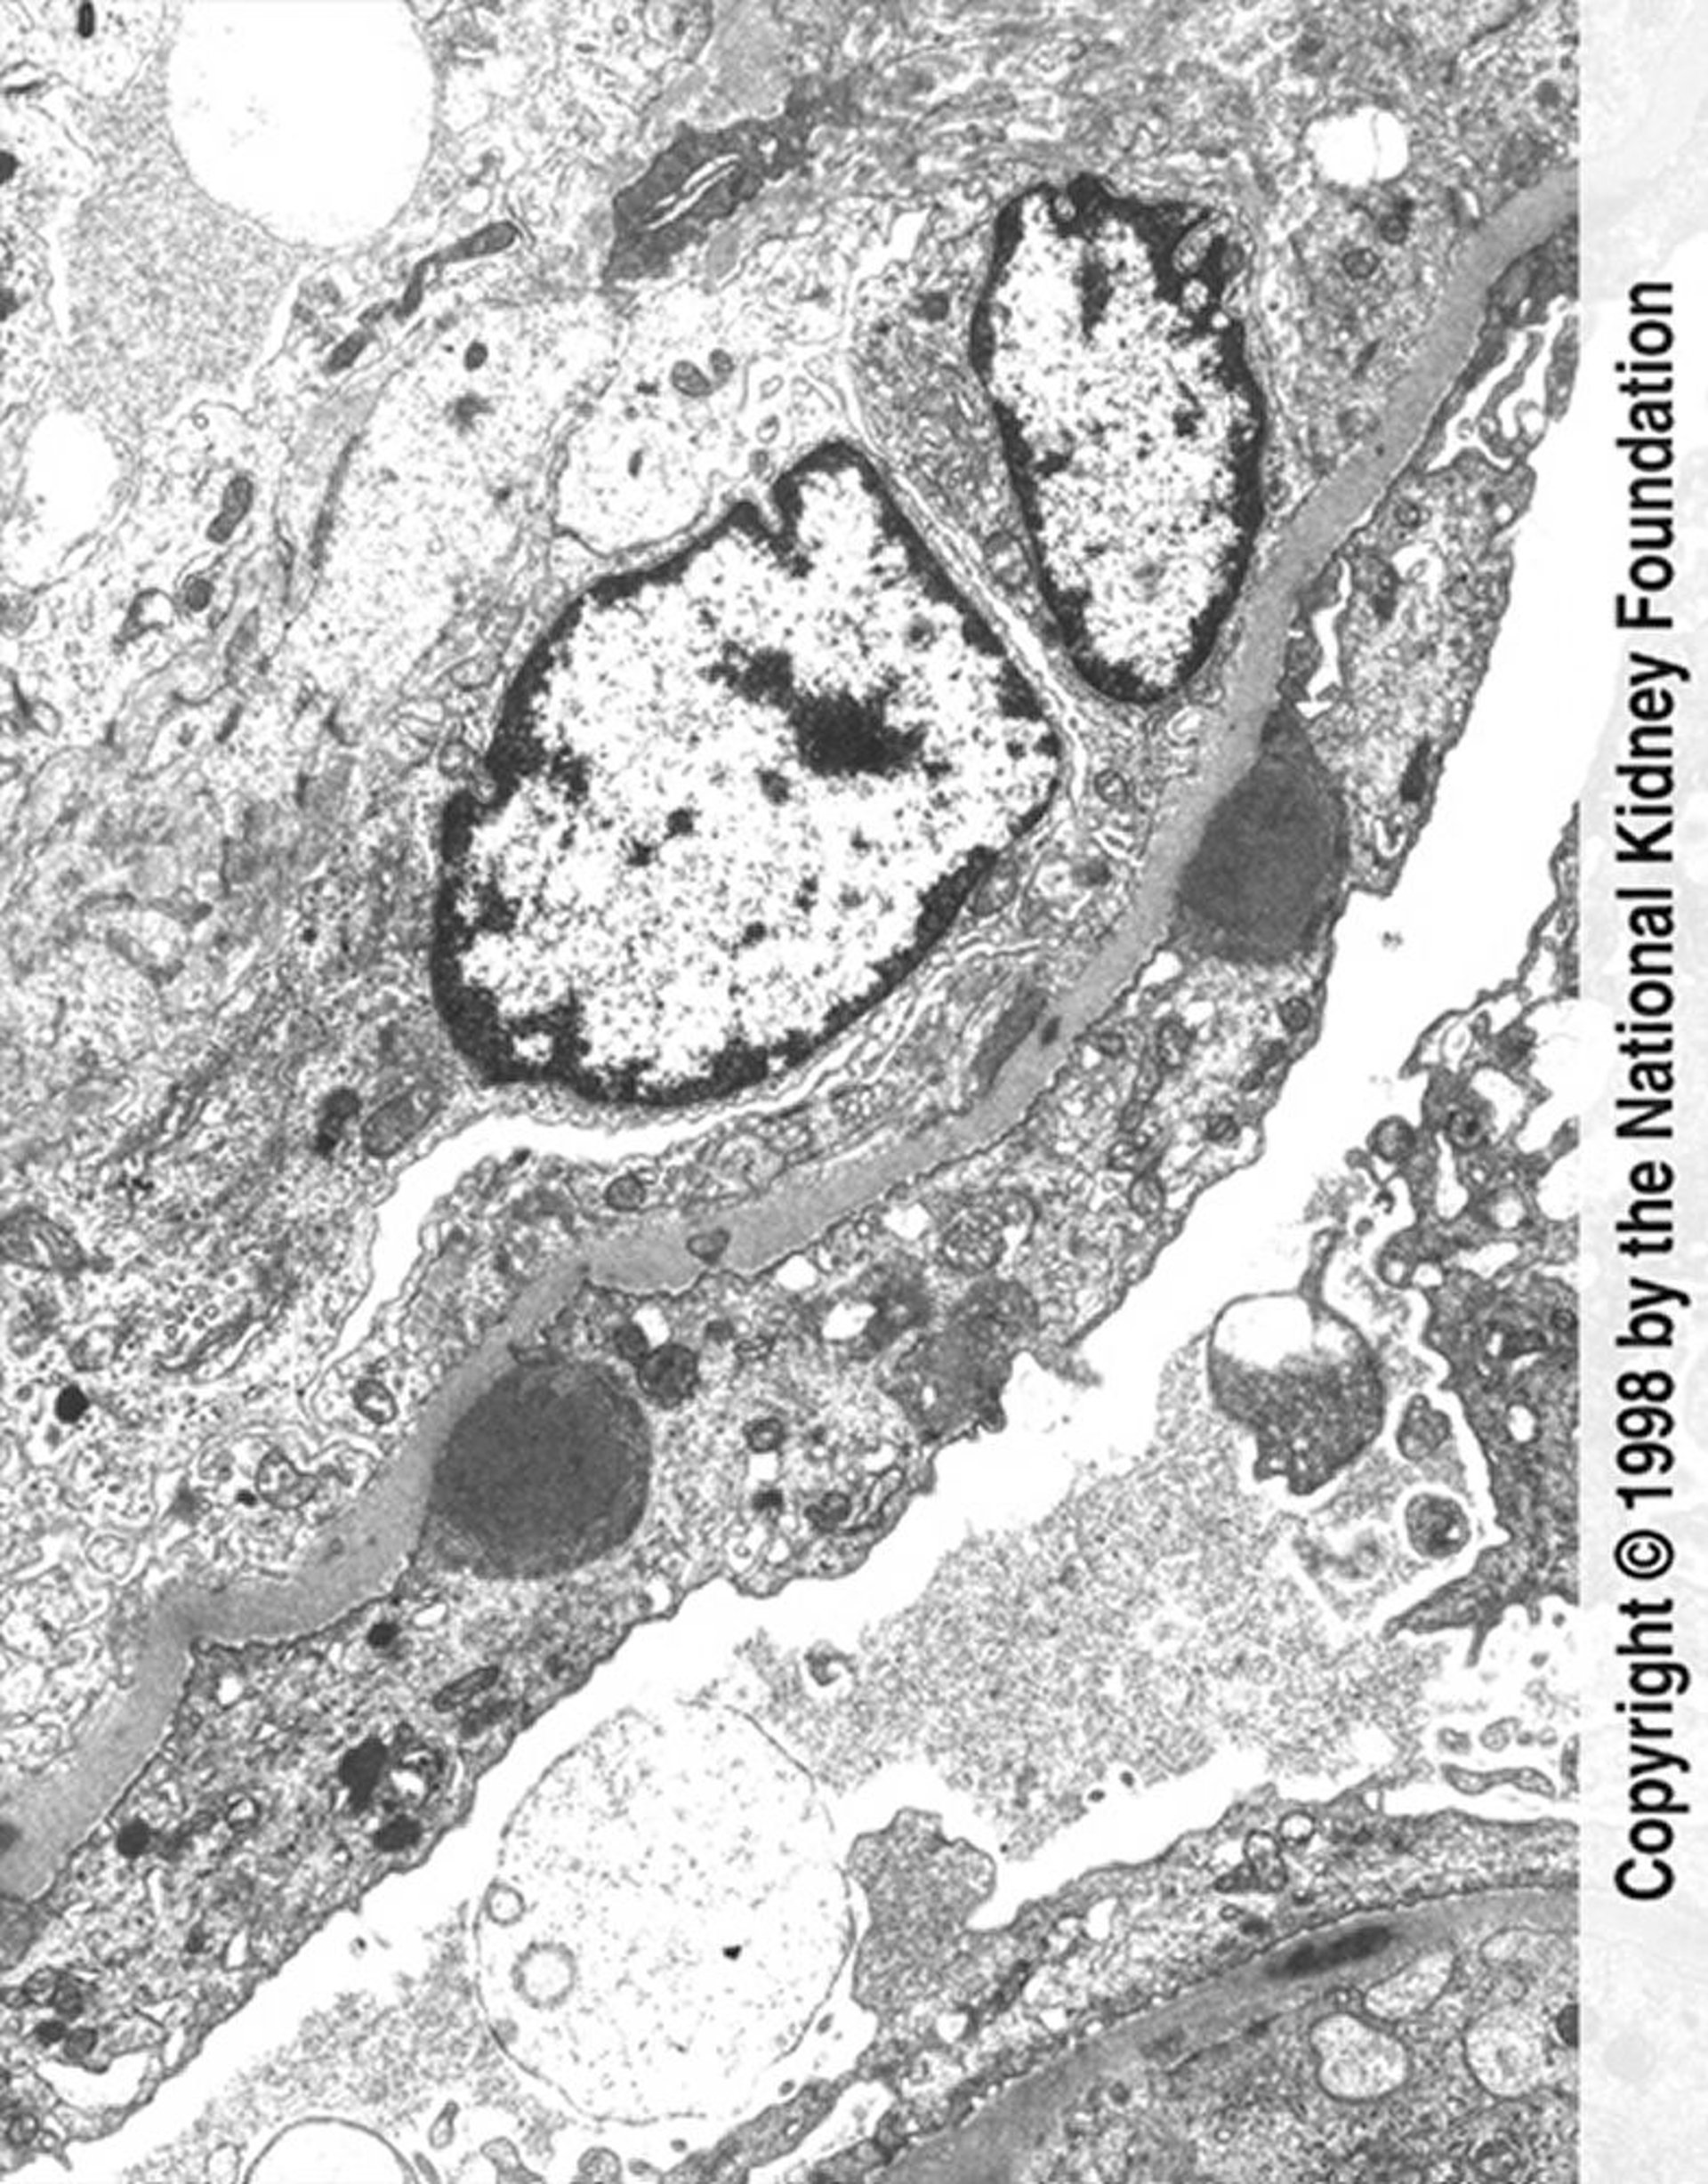

Glomerulonefritis posinfecciosa (depósito de complejos inmunes)

En la microfotografía electrónica de transmisión se observan depósitos de complejos inmunes en forma de giba (gris oscuro) con borramiento extenso de los pedicelos y proliferación endocapilar (×11.250).

Image provided by Agnes Fogo, MD, and the American Journal of Kidney Diseases' Atlas of Renal Pathology (véase www.ajkd.org).